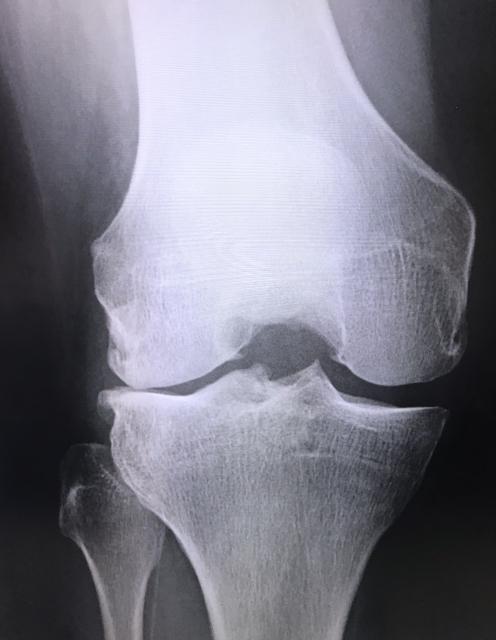

変形性膝関節症

膝の軟骨が「すり減る」は間違い

特に年齢を重ねると顔に垂みが出るように、膝軟骨にも水を含む力が無くなるので、体重の加重により膝軟骨は幅が狭くなってきます。よくすり減ったという表現をするのは、実際に大根おろしですり減るようなものではなく、体重を支えきれずに「へたる」という表現が正しいです。

また若い時に強いケガをした等、古傷がある場合はそこから老化が進むことも多々あります。

年齢に伴い、体重を支えられるだけのクッションが膝になくなってくることで痛みが出現します。最初は立ち上がりの時、階段を降りる時だけですが、そのうち歩くだけでも痛みが出現して辛くなり、初めて病院で診察を受けるケースが多いです。ですが症状が悪化してからだと、クッションである膝軟骨(半月板)は元には戻りません。それは薬は元より、ヒアルロン酸の注射を受けても滑りは良くなりますが、クッションが元に戻ることは現状医学では不可能です。